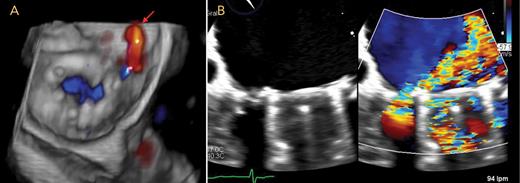

Point-of-care cardiac ultrasonography, performed in the emergency room, revealed normal biventricular function and no evidence of pericardial effusion or clot on the mitral valve. Transesophageal echocardiography showed signs of valvular prosthesis dysfunction, with a paravalvular leak on a posterior ring (Figure). This leak was likely due to the poor quality of tissues, which were friable due to the active infectious process when the valve was implanted. The patient was on transfusion support during the intervention. In the first few days after the procedure, hemolysis improved, with the patient’s LDH measuring 391 IU/L, total bilirubin at 1 mg/dL, and hemoglobin at 8 g/dL.

A: View of the mitral prosthesis from the left atrial aspect, with paravalvular regurgitation depicted with color Doppler, located posterolaterally (arrow). B: Mitral regurgitation with and without color Doppler.